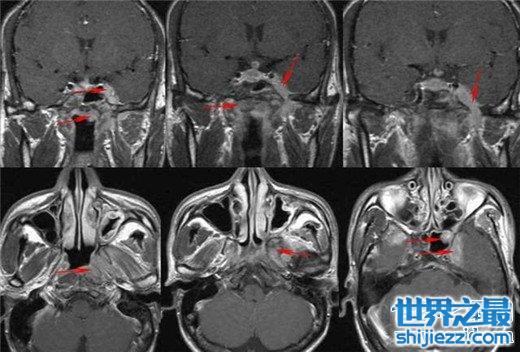

8、鼻咽癌

鼻咽癌在我们国家恶性肿瘤里面,发病人数占到了大约三成左右,是中国十大高发恶性肿瘤之一,很多人都不知道他患了鼻咽癌,因为鼻咽癌的早期症状是不明显的,鼻咽癌形成的主要原因是因为一些慢性疾病,比如说鼻炎之类的,另外就是病毒性感染,最后一个就是喜欢吃腌腊制品。虽然说鼻咽癌他很难发现,但他治愈几率是很大的,大概有60%左右。